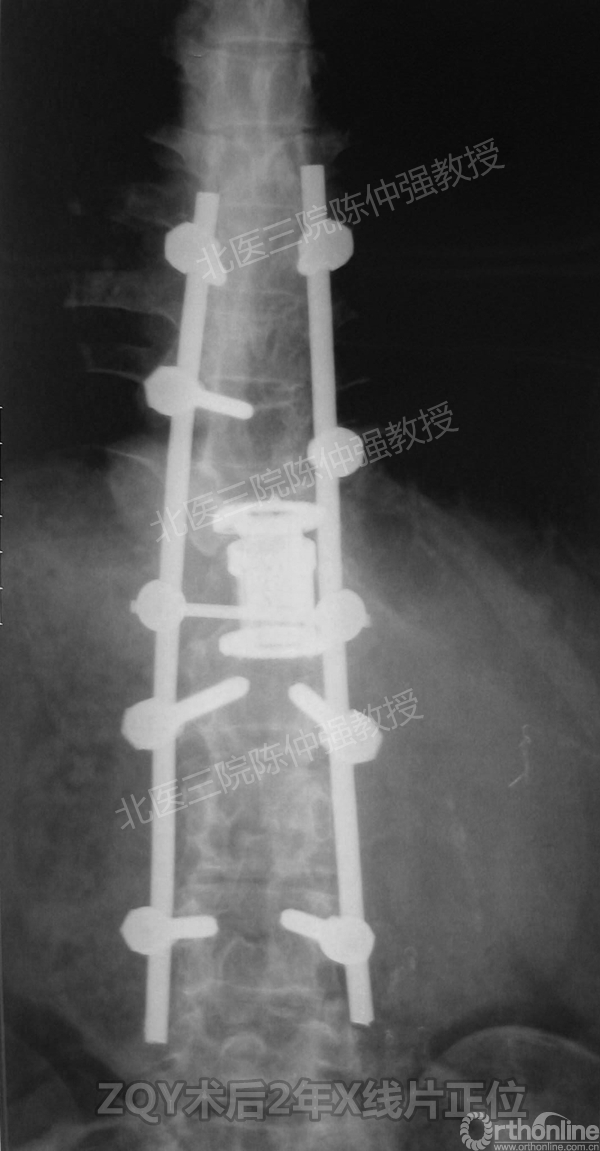

2005年,陈仲强教授在AOSpine年会上分享了一例胸腰椎陈旧结核性侧后凸畸形病例。资料如下:

患者女性17岁,胸腰椎陈旧结核性侧后凸畸形,局部呈“麻花状”扭转,无神经功能受损表现。2005年,陈仲强教授带领团队实施后路+侧前方联合入路脊柱节段切除、双轴旋转矫形术。术后患者外观显著改善,神经功能正常。术后随访证实患者截骨矫形节段骨性融合良好,矫形效果持续良好。